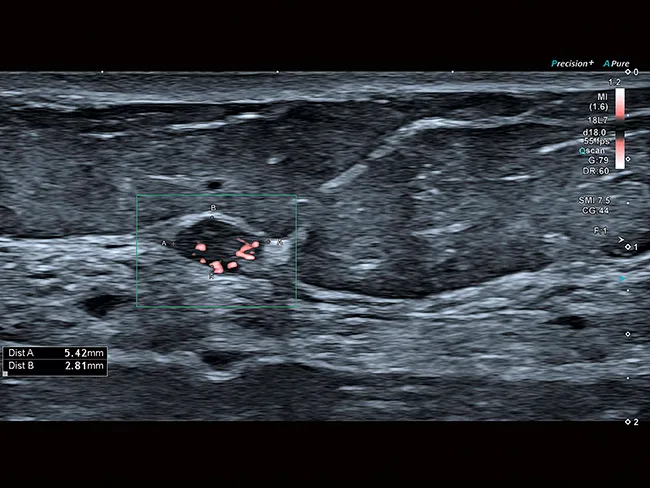

Уровень визуализации сосудов SMI в сочетании с высокой частотой кадров повышает достоверность диагностики при оценке поражений, кист и опухолей.

Aplio обеспечивает цветную допплерографию с превосходным пространственным разрешением, позволяющую выявлять мельчайшие узоры кровотока с беспрецедентной точностью и детализацией при высокой частоте кадров, сохраняя при этом полное качество изображения в режиме B